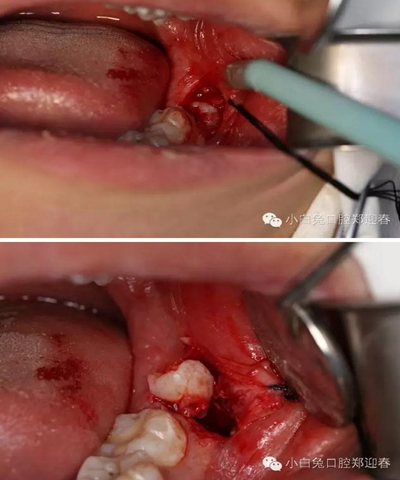

麻醉起效后,按照術(shù)前設(shè)計,行粘膜切開翻瓣。

切口勿偏舌側(cè),頰側(cè)不要越過前庭溝,避免術(shù)后腫脹。

為了防止渦輪高速手機可能的組織纏繞,利用縫合線牽拉切開的瓣膜,充分暴露術(shù)區(qū)。